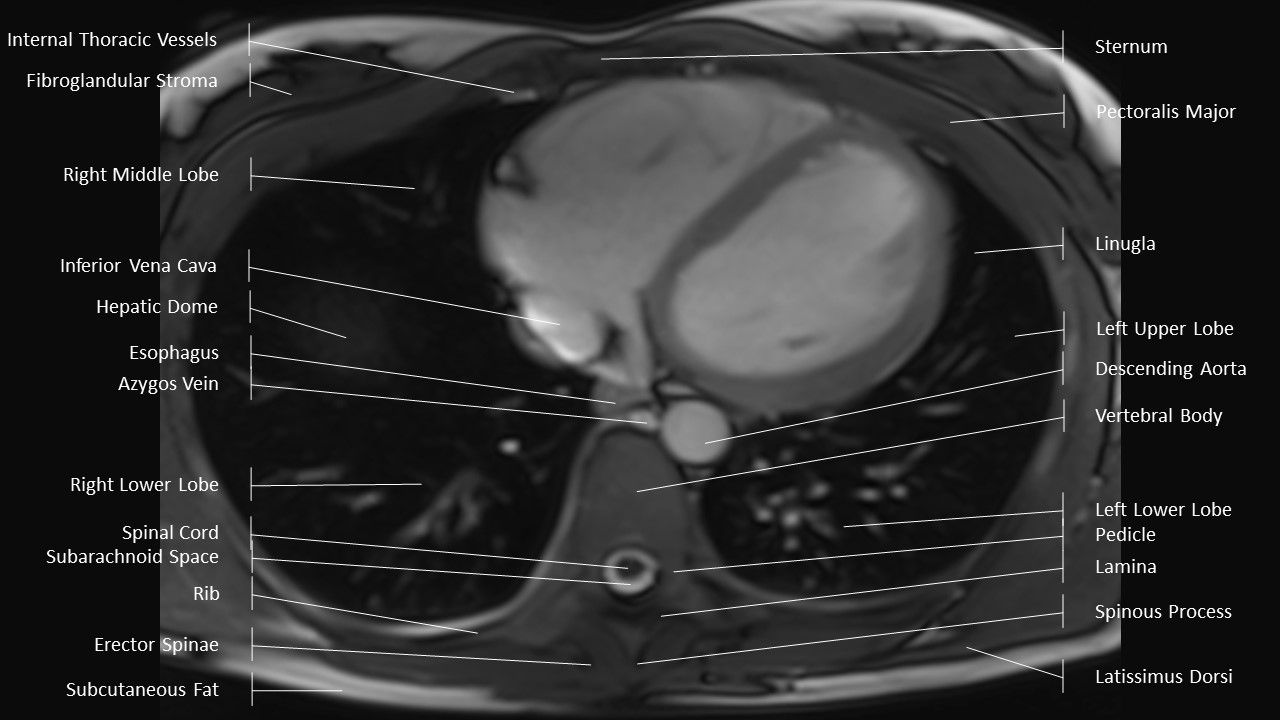

Axial Series